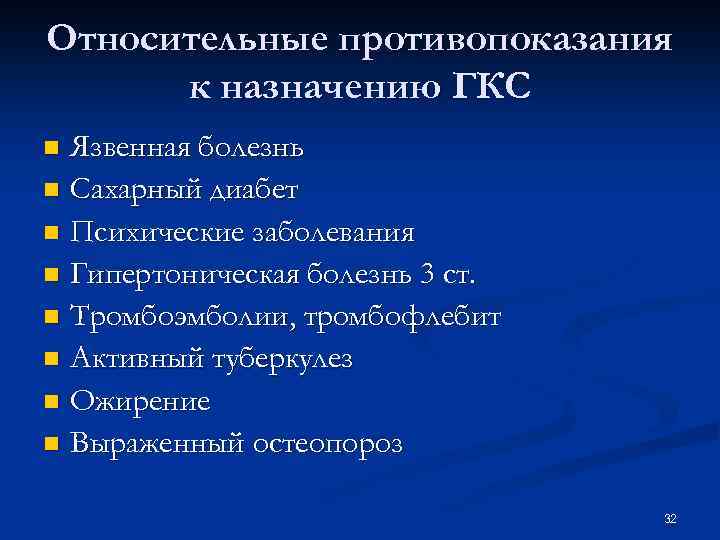

Относительные противопоказания к назначению ГКС Язвенная болезнь n Сахарный диабет n Психические заболевания n Гипертоническая болезнь 3 ст. n Тромбоэмболии, тромбофлебит n Активный туберкулез n Ожирение n Выраженный остеопороз n 32

Относительные противопоказания к назначению ГКС Язвенная болезнь n Сахарный диабет n Психические заболевания n Гипертоническая болезнь 3 ст. n Тромбоэмболии, тромбофлебит n Активный туберкулез n Ожирение n Выраженный остеопороз n 32